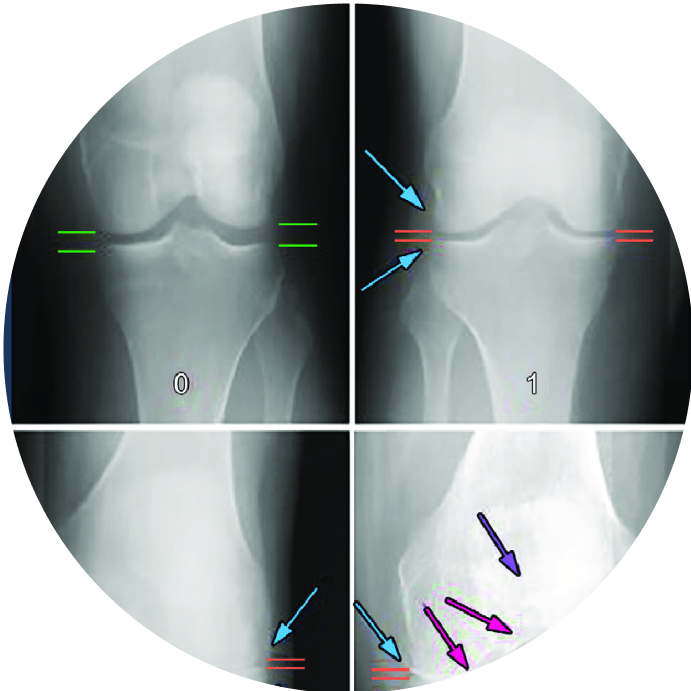

It evaluates various clinical parameters, including reduction in joint space, presence of osteophytes, sclerosis, tibial spikes, bone alignment, and post-operative conditions.

OsteoCheck is a diagnostic system that evaluates bone degeneration, categorizing severity into grades ranging from 1 to 4.